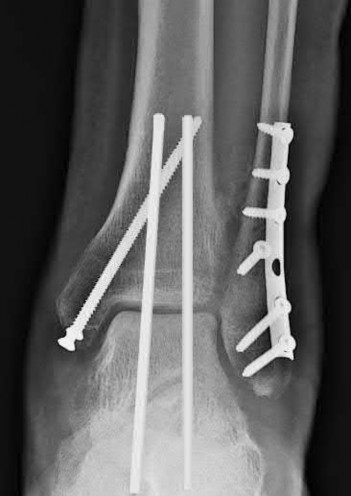

A 25-year-old female is involved in a motor vehicle collision. She presents with the isolated injury seen in Figures A through D. Her leg is swollen but her skin is intact. She has no clinical signs of compartment syndrome. Which of the following treatment options will allow for maintenance of fracture alignment and minimize the risk of soft tissue complications?

The patient presents with a closed distal third metaphyseal-diaphyseal distal tibia fracture with simple intra-articular extension. Immediate intramedullary nailing along with percutaneous fixation of the articular component provides appropriate restoration of length, rotation and alignment and minimizes the risk of wound complication.

Displaced distal third tibia fractures may be associated with simple intraarticular extension. Operative treatment of intra-articular distal tibia fractures has historically been performed with open reduction and internal fixation. Early open reduction and plate fixation of pilon fractures has been associated with high rates of infection and wound complication. In select patterns with simple articular extension, percutaneous screw fixation and medullary nailing may provide appropriate reduction with minimal soft-tissue risk.

Marcus et al. evaluated the outcomes of immediate intramedullary nailing and percutaneous fixation of simple intra-articular distal tibia fractures (AO/OTA 43 C1 and C2). The authors found excellent rates of union and alignment, however caution against broad application of this technique until more rigorous randomized studies can be performed.

Sirkin et al. retrospectively evaluated the results of a staged approach to management of intra-articular distal tibia fractures with temporary bridging external fixation followed by open reduction and internal fixation (ORIF). The authors found decreased rates of wound complication and infection compared with prior studies.

Figures A and B demonstrate a distal third tibial shaft fracture with simple intra-articular extension. The axial and coronal CT cuts in Figures C and D further clarify the articular injury. Illustrations A and B demonstrate a comminuted distal third tibial fracture with simple intra-articular extension. Illustrations C and D are fluoroscopic images of the same injury after intramedullary nailing and percutaneous fixation of the articular component.